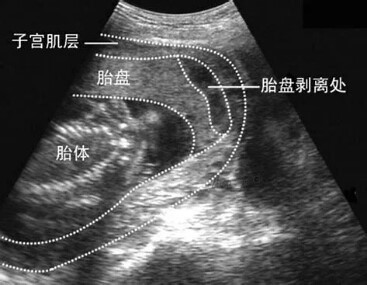

B超很快做好了,结果显示胎盘增厚且胎盘后方多个血池,但是她整个孕期并无胎盘血池的记录。因此,我们比较明确了这是胎盘早剥,是不典型的胎盘早剥!这时抽血化验结果也出来了,D-二聚体高达1万多。